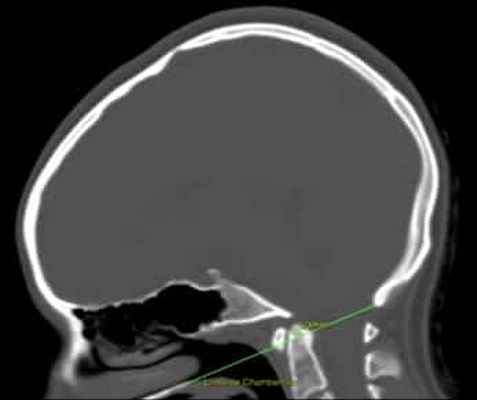

Рисунок 1. Базиллярная импрессия. КТ головного мозга с линией Чемберлена, которая соединяет заднюю стенку большого затылочного отверстия с передней стенкой твердого нёба и должна проходить по верхней части атланта. В данном случае атлант превышает границу на 5,3 мм.

Диагноз ставится при помощи измерения линии Чемберлена и/или других показателей (см. Рис.1).